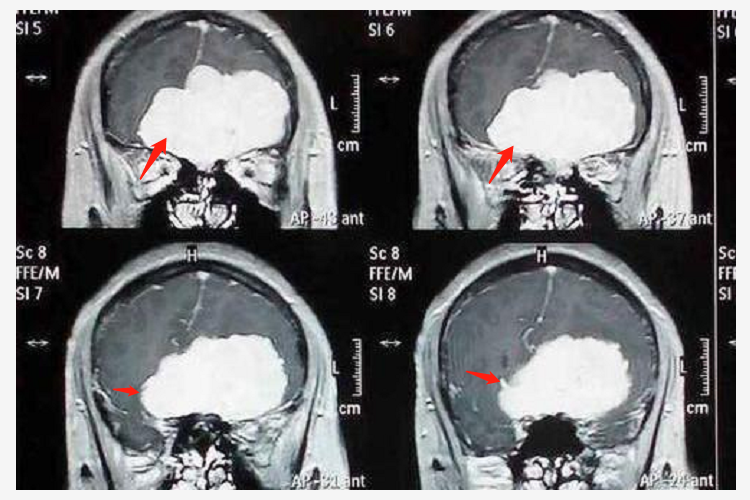

4、诊断方法:头颅CT和MRI是诊断嗅沟脑膜瘤的主要方法,CT可显示肿瘤的位置、大小、形态、钙化情况以及与周围骨质的关系,MRI能更清晰地显示肿瘤与周围软组织结构的关系,以及肿瘤的血供情况。